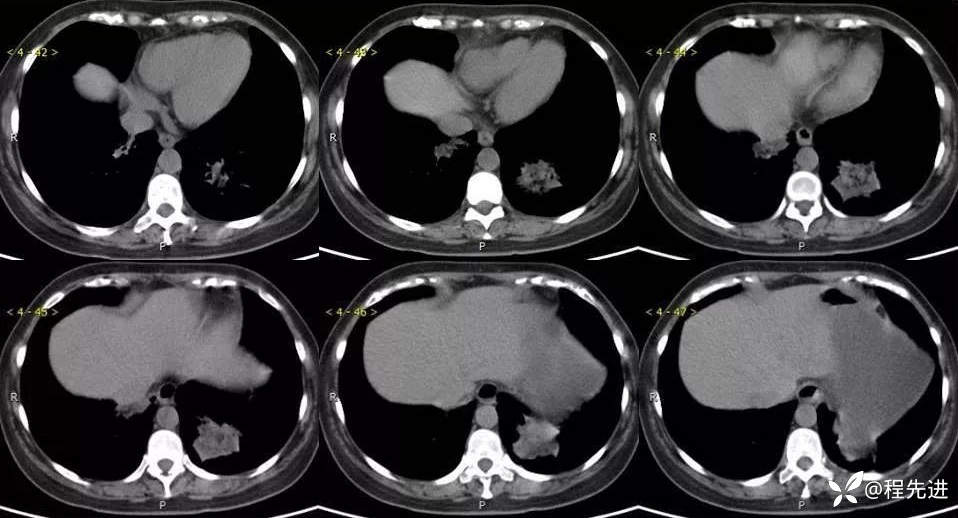

主诉:体检发现肺结节2周

现病史:患者2周前体检时发现两肺多发高密度影。无咳嗽、咳痰,无咯血、呼吸困难,无胸闷、胸痛,无发热、潮热盗汗。